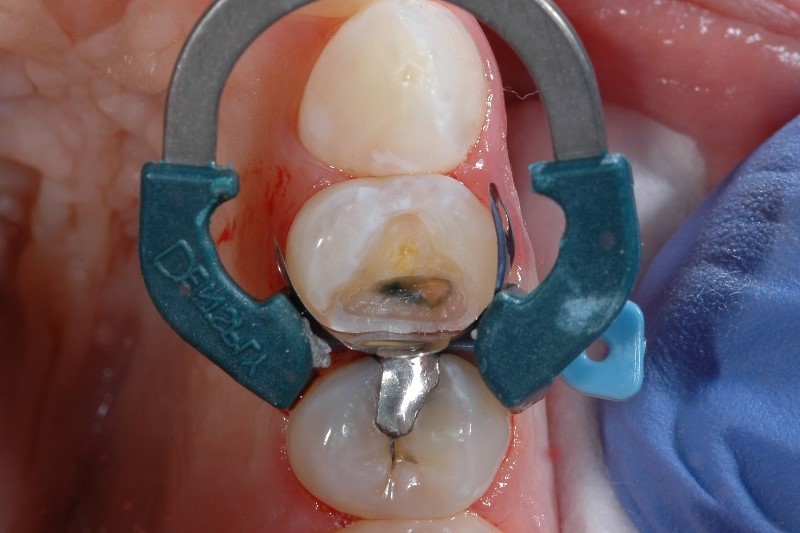

It's not uncommon for a dental practitioner to have a fully booked schedule for the day, when a patient calls complaining of post-operative sensitivity from their recent Class II composite procedure. After working the patient into the schedule, diagnosing what initially caused the sensitivity can be stressful and challenging given how technique sensitive these procedures are.

What causes post-op sensitivity after composite fillings? Quite a few things, actually - placing composite resins is a complex procedure considering the nature of dentin is close to the pulp, and some studies have estimated sensitivity occurs after 10-15% of posterior composite restorations.1

The following are challenges practitioners report that can lead to postoperative sensitivity in composite restorations as well as tips for prevention in your next procedure.